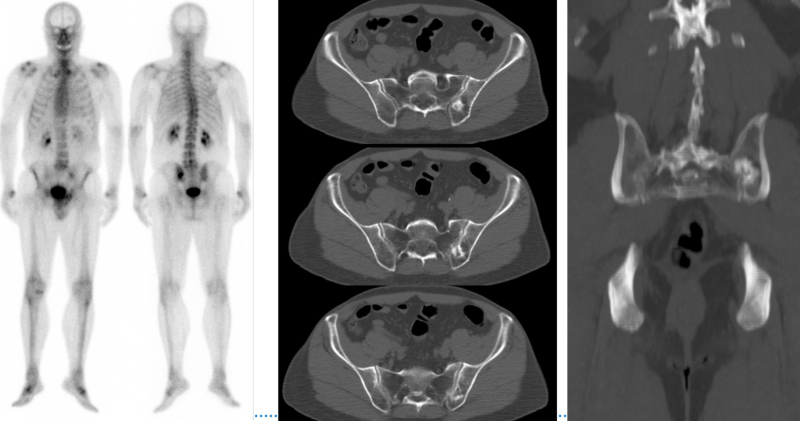

Hombre de 69 años, atleta, con diagnóstico reciente de adenocarcinoma de próstata, Gleason 3+3, PSA 4,2 ng/ml, al que se realiza centellografía ósea para estadificación (fig.1). Se observó la presencia de imagen hipercaptante única en tercio medio de la unión sacroilíaca izquierda. Este foco se correspondió con imagen lítico-blástica por CT en la porción posterior del ilíaco izquierdo, adyacente a la articulación sacroilíaca. Posteriormente se realiza estudio PET/CT F18-colina para descartar o confirmar carácter maligno de la lesión en base a su afinidad por el radiofármaco. Se comprobó captación leve de F18-colina en la lesión, consistente con proceso inflamatorio no tumoral (fig. 2). Se interpretó como geoda acompañada de reacción inflamatoria local. El tumor primario de próstata, a su vez, presentó captación intensa del trazador.